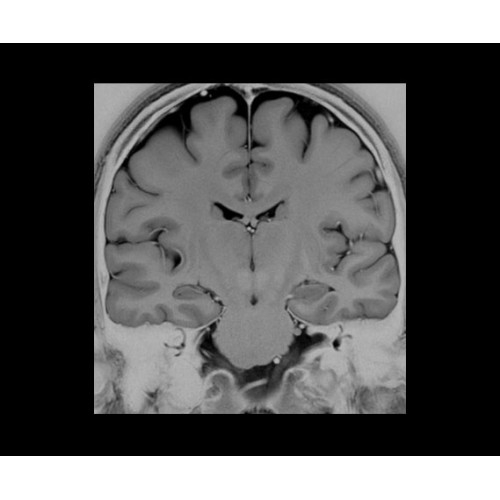

• NeuroWorks — универсальное решение для визуализации анатомии головного мозга, позвоночника, сосудов и периферических нервов с четкой дифференциацией тканей.

Теперь возможности МРТ поражают еще больше благодаря ультрасовременным решениям для визуализации с SIGNA Architect 3.0 Тл, объединяющей новейшие достижения в области МР-технологий и интуитивно понятный интерфейс. Система SIGNA Architect, разработанная на базе новой платформы SIGNA Works, представляет собой гармоничное сочетание дизайна и функциональности. Каждый элемент системы направлен на повышение производительности, эффективности клинической практики, финансовых показателей, а также комфорта и безопасности пациента.

• 48-канальная катушка TDI для головы, входящая в базовую комплектацию SIGNA Architect, обеспечивает феноменальную производительность с учетом особенностей каждого пациента. Благодаря гибкому и универсальному дизайну, высокому соотношению сигнал/шум и передовым технологиям визуализации, таким как HyperWorks, учитываются потребности подавляющего большинства пациентов.